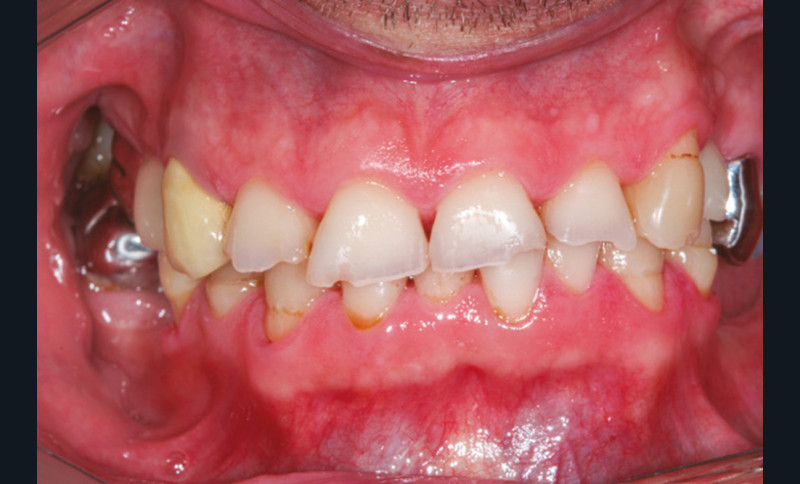

La version des dents distales peut aussi avoir des conséquences parodontales désastreuses : sur un parodonte réduit, une hypermobilité peut se développer, une poche parodontale peut aussi apparaître. Chez un patient parodontal, un « effet domino » est possible, des extractions non compensées diminueront donc le pronostic des dents restantes (fig. 7 à 9).

Le principe de protection mutuelle implique que les dents postérieures protègent les antérieures lors de la mastication. Des extractions non compensées de molaires, par exemple, entraîneront une hypersollicitation des antérieures et une usure importante du fait du principe de calage ainsi qu’un risque de perte de dimension verticale (fig. 10 à 13).